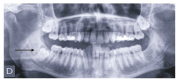

Material and method: We sent letters to 931 registered dentists in Biscay, with an explanation of the study objectives, description of a case of lower third molar impaction, including a panoramic radiograph, and a questionnaire. The questionnaire asked whether they would prescribe antibiotics and/or antiseptics, in the hypothetical case of lower third molar extraction surgery presented, and if so, when, what type, at what dose and how long for.